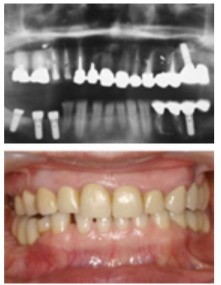

手前から第一大臼歯、第二大臼歯という名前で、他の歯と比べてとにかく大きいのが特徴です。

その大きさから噛む力が強く、食物を潰し食べやすくするのに最も活躍する歯です。

特に第一大臼歯は主機能部位と呼ばれ機能的にもっとも重要な歯と考えられています。

しかし奥の方にあって磨きにくいこと、小児期に生えてきたことに気づきにくいこと、過大な負荷がかかることなどから最も失われやすい歯であるとも考えられています。

ブリッジは宙づりのダミーの歯(ポンティック)に力がかかると大きくたわみます。

その距離が長ければ長いほど大きくたわむようにできており、ポンティックの距離が2倍になればたわみは4倍、3倍になれば9倍と距離の2乗程度たわむと言われています。

ポンティックに負担がかかりたわんだブリッジは「く」の字型に曲がり接着剤が流れ出し、外れたり虫歯になったりする可能性が高まります。

最も噛むのに重要で、かつ最も失われる確率の高い第一大臼歯はすべての歯の中で最も前後的な横幅(近遠心的幅径)が長いので他の歯に比べてブリッジを作った際のたわみ量が大きくなります。

また第一大臼歯喪失時のブリッジは手前の第二小臼歯、後ろの第二大臼歯を削って作ります。

人の口の構造上、後方に行けば行くほど歯茎の位置が高くなり、相対的に後方の歯ほど歯の見えている部分身長が低くなります。

歯の見えている部分が短いとブリッジが引っかかる面積も少なくなり外れやすくなってしまいます。

身長の低い第二大臼歯にブリッジの片棒を担がせるのも第一大臼歯欠損時のブリッジの不利な点となります。

これらの理由から、同じ歯を一本失った時のブリッジであっても部位によってその予後に大きな差がでると言われています。部分入れ歯もこの場合は不向きです。